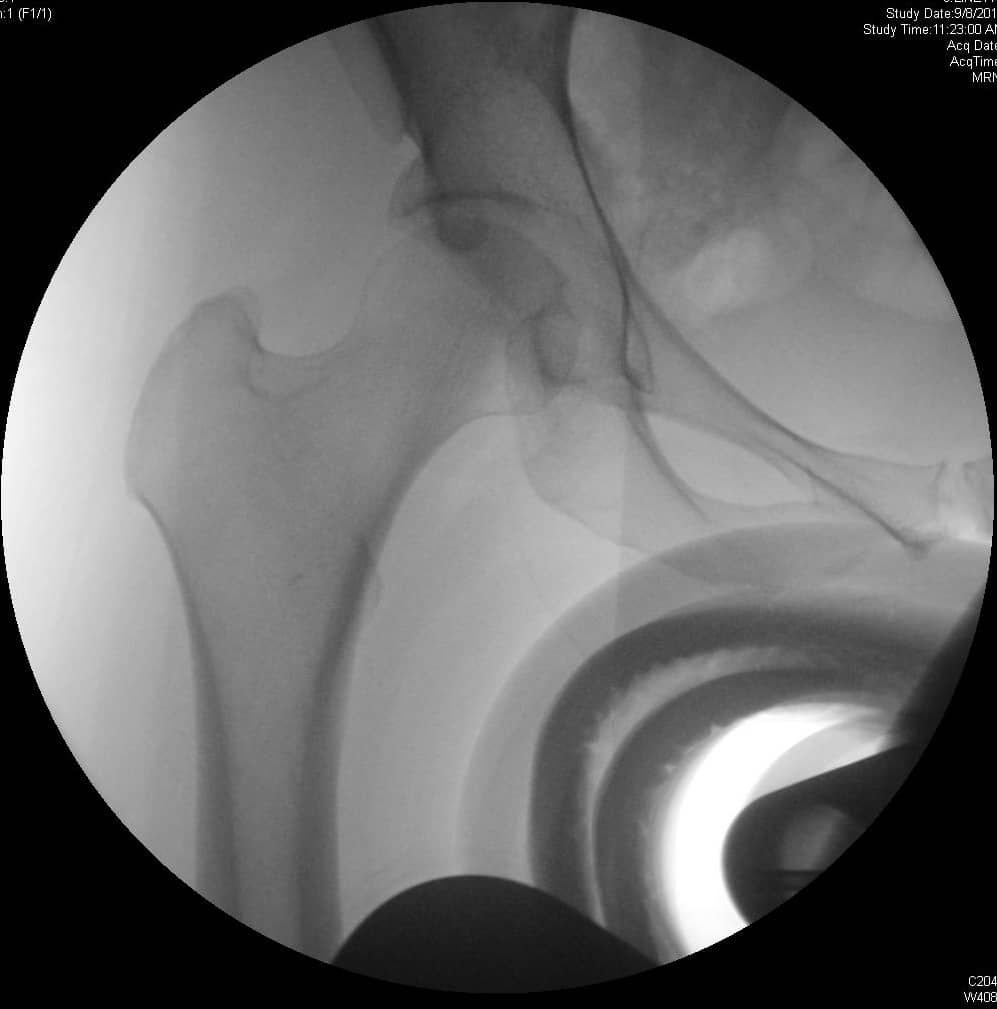

एमआरआई और सीटी का उपयोग एसिटाबुलम और समीपस्थ फीमर के आगे के मूल्यांकन के लिए किया जा सकता है। ये अध्ययन एसिटेबुलर संस्करण और नरम ऊतक के प्रभाव का बेहतर मूल्यांकन प्रदान कर सकते हैं या प्रीऑपरेटिव प्लानिंग में मदद कर सकते हैं। एमआर आर्थ्रोग्राम ऊरु गर्दन के कैम घाव के निदान में भी सहायता कर सकता है, लैब्रम या उपास्थि का आकलन कर सकता है। रेडियल अनुक्रमण सबसे अच्छा है, एक असामान्य लैब्रम कुंद दिखाई देगा या इसके आधार पर बढ़े हुए संकेत के साथ दिखाई देगा। 3, 4 एसिटैबुलर रेट्रोवर्जन के कारण पिंसर का प्रभाव, शुरू में लैब्रल विफलता दिखाएगा, जिसके बाद एक कॉन्ट्राकूप तंत्र के परिणामस्वरूप पोस्टरोहीन एसिटेबुलर कार्टिलेज में छोटे, पतले घाव होंगे। 5 इसे क्रॉस-ओवर संकेत, पीछे की दीवार के संकेत, या रेडियोग्राफ़ पर एक नकारात्मक खट्टा कोण के साथ पुन: प्रदर्शित किया जा सकता है। एमआरआई में कुंद लैब्रम, ऊरु गर्दन पर चुंबन घाव, पीछे के एसिटेबुलर कार्टिलेज का घिसना, या एक रेट्रोवर्टेड एसिटाबुलम प्रदर्शित होगा। ऊरु गर्दन के घावों के कारण कैम का प्रभाव, उपास्थि की प्रारंभिक विफलता को दर्शाता है, जिसके बाद लैब्रल फट जाता है। पार्श्व एक्स-रे पर सिर-गर्दन ऑफसेट में कमी, ऊरु गर्दन पर अतिरिक्त हड्डी की आकृति और बढ़े हुए अल्फा-कोण का आकलन निदान में सहायता कर सकता है। एमआरआई पर लैब्रम अपने आधार पर फटने का प्रदर्शन कर सकता है, एक असामान्य ऊरु सिर-गर्दन समोच्च स्पष्ट हो सकता है, या उपास्थि प्रदूषण स्पष्ट हो सकता है। रोगी 80% मामलों में कैम और पिंसर दोनों के साथ पेश होंगे, हालांकि एक रूप आमतौर पर प्रमुख होता है। 2

- एफएआई के मूल्यांकन के लिए एक क्रॉस-टेबल पार्श्व दृश्य महत्वपूर्ण है, जिससे एंटेरोलेटरल फेमोरल गर्दन का दृश्य देखने की अनुमति मिलती है।

- अल्फा-कोण: ऊरु गर्दन की मध्य रेखा के साथ एक रेखा और ऊरु सिर के केंद्र से उस बिंदु तक एक रेखा के बीच बनता है जहां अतिरिक्त हड्डी सामान्य ऊरु सिर स्फेरिसिटी से विचलित होती है। 60 डिग्री से अधिक का कोण एफएआई को इंगित करता है।

- सिर-गर्दन ऑफसेट: ऊरु गर्दन के अनुदैर्ध्य अक्ष को विभाजित करने वाली रेखा से शुरू करें। एक समानांतर रेखा खींचें जो ऊरु गर्दन के पूर्ववर्ती पहलू के लिए स्पर्शरेखीय है और पूर्ववर्ती ऊरु सिर के समानांतर रेखा स्पर्शरेखा की दूरी को मापें। सामान्य दूरी 9 मिमी से अधिक है या सिर के व्यास का अनुपात 0.17 से अधिक है।